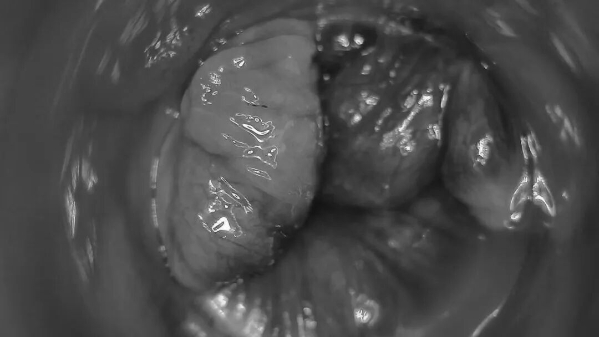

电子肛门镜,通过前端安装的微型摄像头,将肛门、直肠下段的黏膜状况实时放大显示在屏幕上,打破传统指诊无法直接观察肛门内部的弊端。

方便医生清晰观察病灶位置、大小及形态,同时可将病灶打印成像,亦可放大观察,为治疗前后的对比提供依据,帮助患者了解病情、选择治疗方案,避免因传统人为检查不足而造成病情延误。

电子肛门镜可检查患者痔疮类型(内痔/外痔/混合痔),以及内痔有无糜烂、充血,了解痔疮严重程度。

直肠黏膜脱垂患者,通过电子肛门镜可观察到松散黏膜向下脱垂。

电子肛门镜检查,能观察到直肠下段黏膜,是否存在充血、水肿、糜烂、溃疡等炎症。